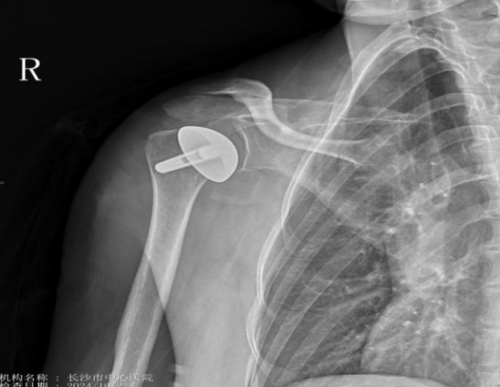

术后影像

运动医学、创伤、关节、骨病科主任丑克表示,肩关节表面置换术,即对肱骨头表面进行置换,术中磨去肱骨头的软骨部分,然后在肱骨头原解剖位置安装内侧表面为纯钛+羟基磷灰石(HA)双涂层的帽状金属假体,从而代替肱骨头表面磨损的软骨。该类手术是目前较高层次的骨科手术,手术操作具有一定的难度,但这种方法治疗彻底,术后患者的疼痛缓解率高,具有并发症少等优势。